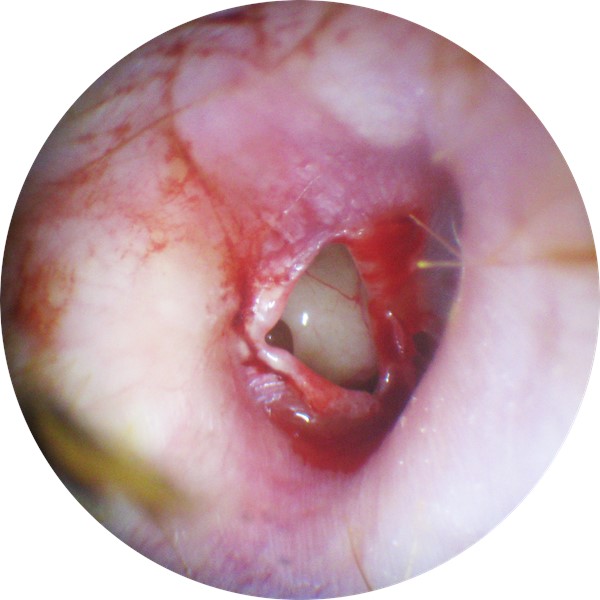

| TEED 5 |

Free hemorrhage into the middle ear, tympanic membrane perforation; blood may be visible outside or within the external auditory canal. |

|